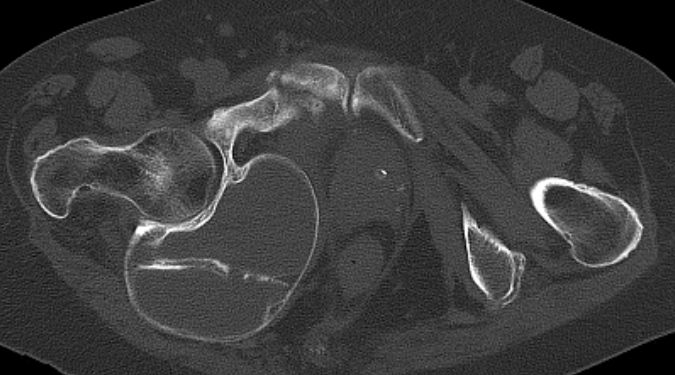

81-jährige Patienten mit Endometriumkarzinom von 23 Jahren. Jetzt ossäre Metastase des vorderen rechten Schambeins mit pathologischer Fraktur. Zystische Raumforderung dorsal seit 8 Jahren unverändert.